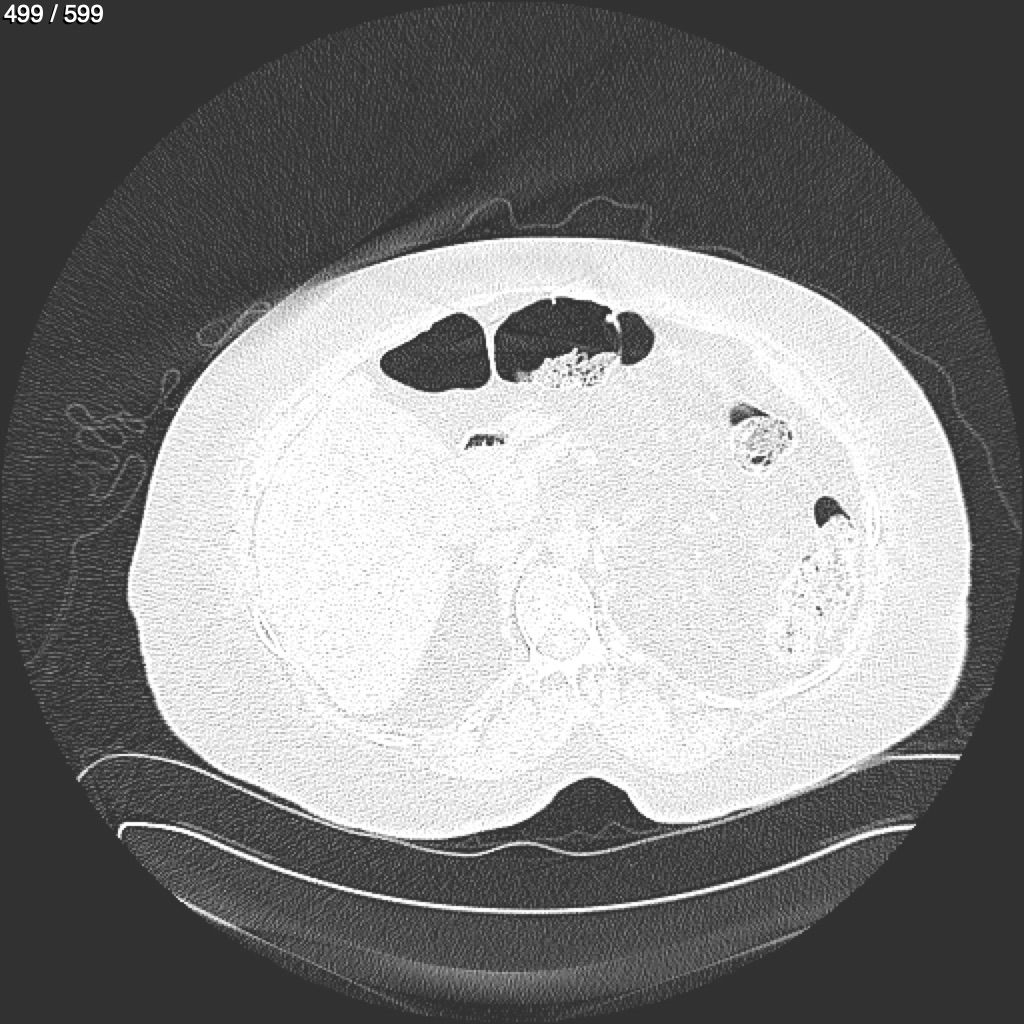

Home G​l​o​r​i​a​ ​G​l​a​d​y​s​ ​B​e​a​s​l​e​y​ ​-​ ​T​ó​r​a​x​ ​T​o​r​a​x​_​S​i​m​p​l​e​ ​(​A​d​u​l​t​o​)